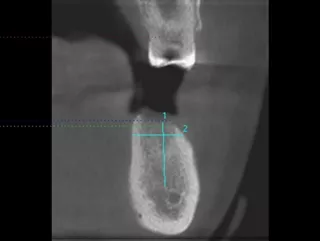

• CBCT analysis reveals available bone before implantation.